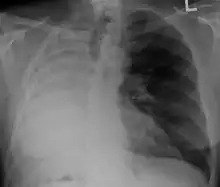

![]() Appearance of the cut surface of a pneumonectomy specimen containing lung cancer, here a squamous cell carcinoma (the whitish tumor near the bronchi). | |